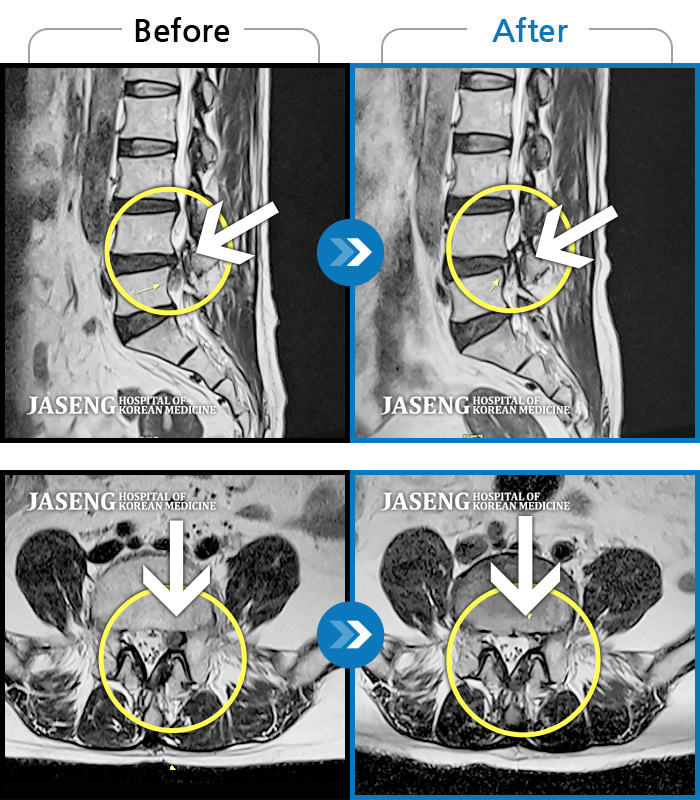

Before

After

환자에게 사전 동의를 받아 동일 조건에서 촬영되었습니다.

개인에 따라 치료 후 부작용이 발생할 수 있으니 의료진과 상담 후 치료를 진행하시기 바랍니다.

요통 및 우측 골반 통증, 우측 대퇴부 외측 통증

허리디스크로 인한 요통, 좌측 하지방사통